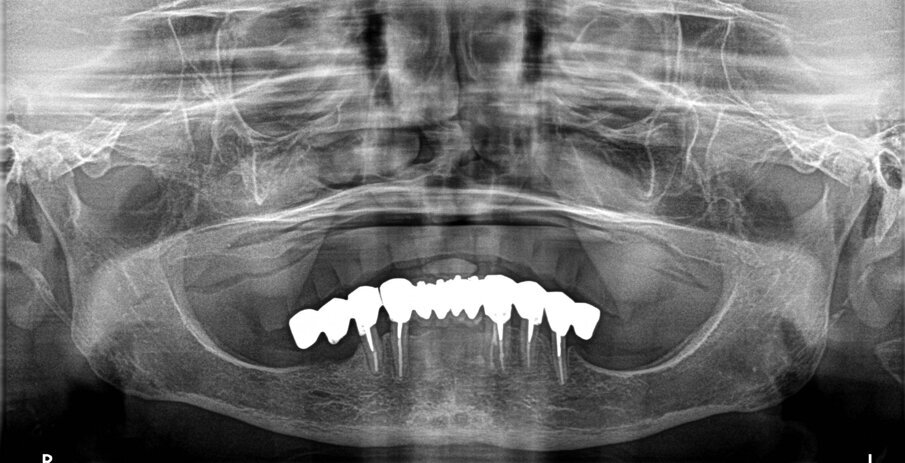

Una paziente di 73 anni lamentava mobilità a una porzione di protesi fissa nel settore 4. All’osservazione clinica e radiografica (Fig. 1), si evidenziava che il pilastro in posizione 45 si era decementato ed era stato completamente distrutto dalla carie. A seguito del sovraccarico il connettore tra i denti 43 e 44 si era fratturato e questo causava mobilità al dente 44 per trauma occlusale. Nonostante il ponte fosse stato realizzato molti anni prima la paziente desiderava mantenere la parte ancora funzionante e sostituire solo i due denti mancanti nel settore 4. Il ponte è stato sezionato tra i denti 44 e 45 e i due denti a sbalzo sono stati rimossi.

Il connettore è stato arrotondato e lucidato e nessun altro intervento è stato eseguito sulla protesi preesistente. All’anamnesi la paziente comunicava di essere in terapia con anticoagulanti a causa di stent coronari applicati circa 5 anni prima. Al momento godeva di buona salute e agli esami clinici e strumentali non si evidenziavano problemi cardiaci. È stata eseguita una dental-scan (Fig. 2), dalla quale si evidenziava che in posizione 46 l’osso residuo al di sopra del canale mandibolare misurava circa 4,5 mm.

A causa della terapia anticoagulante si decise di non eseguire procedure di aumento dell’osso, perché la paziente le percepiva come troppo invasive e aveva timore di sanguinamenti copiosi dopo la chirurgia o di ecchimosi ed edemi molto estesi e persistenti per lungo tempo. Si decise quindi di inserire, in posizione 46, un impianto extracorto di 4,5 mm di lunghezza.

A sei mesi dalla consegna delle corone è stata eseguita un Rx endoorale di controllo da cui si evidenziava una buona stabilità dell’osso marginale (Fig. 11).